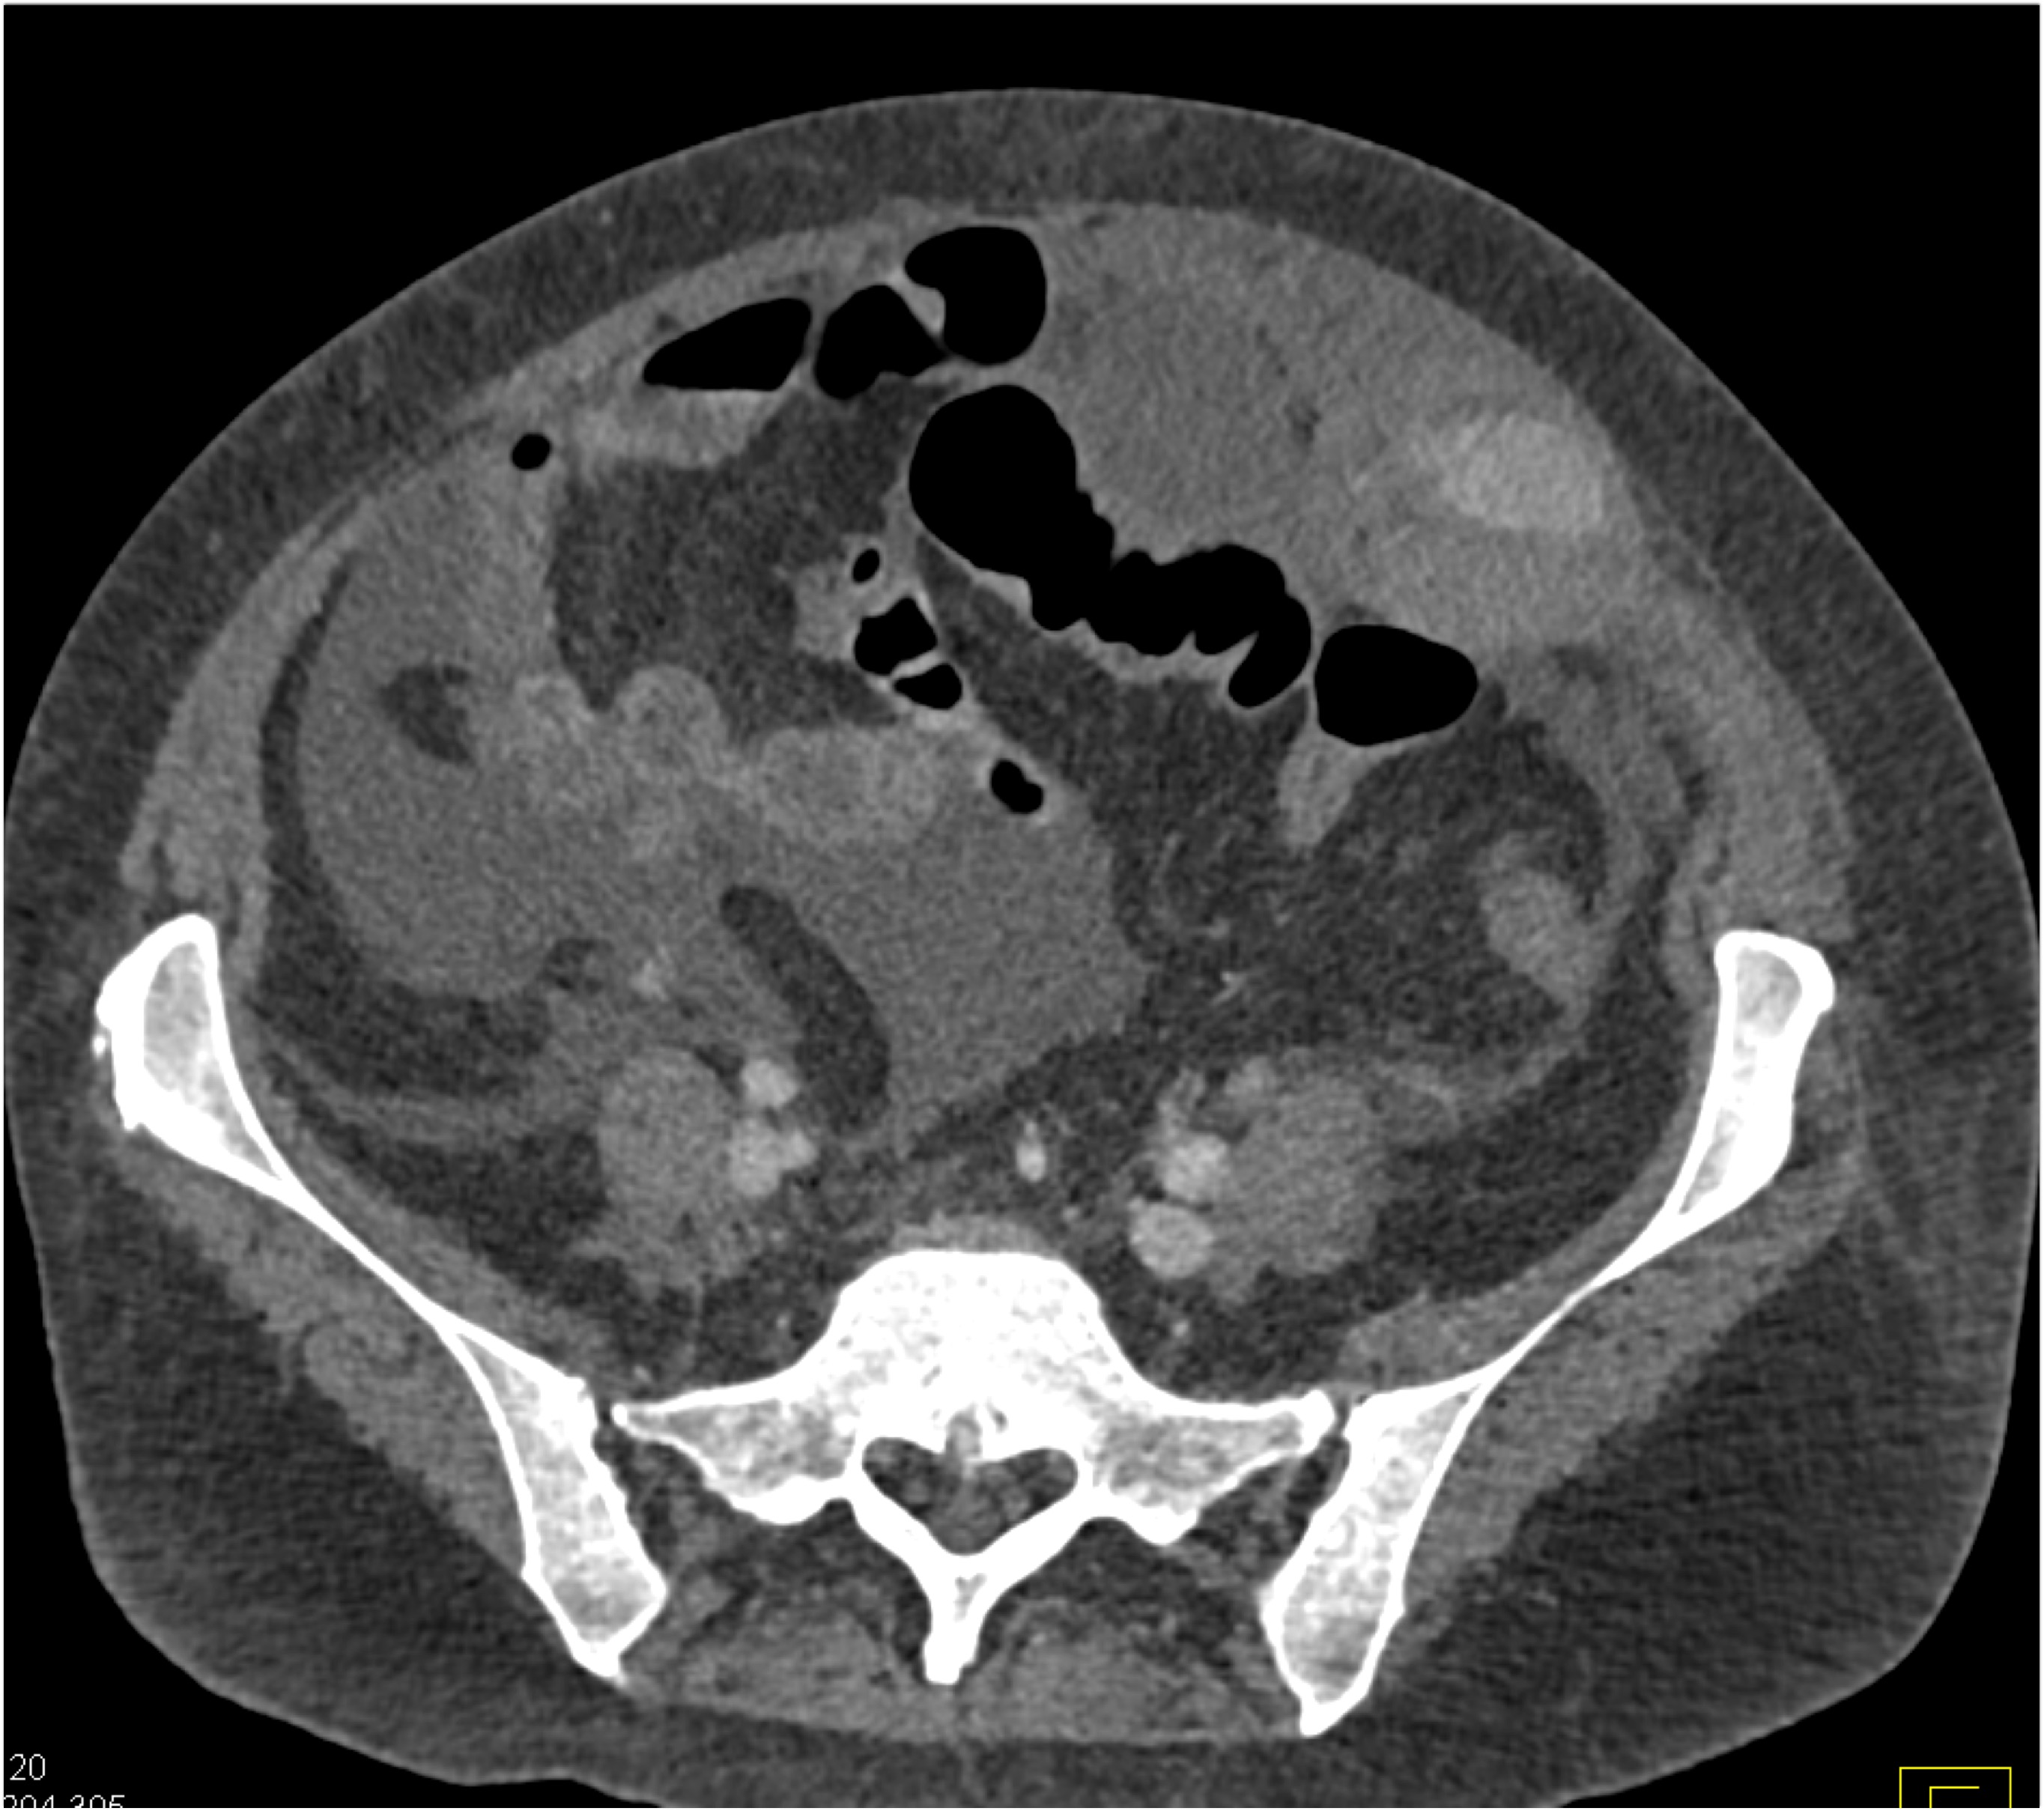

5) In this patient with Crohn’s disease and abdominal pain the critical CT finding is

stricture of colon

bowel wall thickening

active GI bleed

superimposed colon cancer